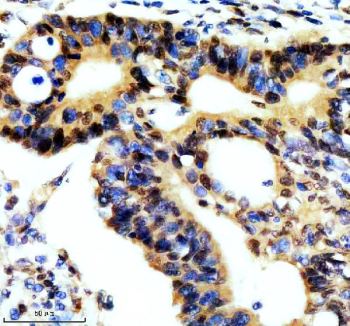

Immunohistochemical staining of REST using anti-REST antibody. REST was detected in a paraffin-embedded section of human thyroid cancer tissue. Heat mediated antigen retrieval was performed in EDTA buffer (pH 8.0, epitope retrieval solution). The tissue section was blocked with 10% goat serum. The tissue section was then incubated with 2 ug/ml rabbit anti-REST antibody overnight at 4oC. Peroxidase Conjugated Goat Anti-rabbit IgG was used as secondary antibody and incubated for 30 minutes at 37oC. The tissue section was developed using an HRP secondary and DAB substrate.